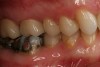

Figure 17  Occlusal view of cemented crowns for teeth Nos. 2 and 3.

Figure 17

Figure 18  Facial view of the cemented crowns for teeth Nos. 2 and 3.

Figure 18

The milled and sintered zirconia substructure is fit to the SLA die model. The external surface of the zirconia substructure is air-abraded using Rocatec™ Soft (3M ESPE) to prepare it for fusion to the digital veneer. The digital veneer is carefully cut from the block holder and placed in distilled water for 1 minute to allow water to uniformly penetrate into the glass ceramic. The Lava DVS Fusion Porcelain is mixed in one of the 10 shades appropriate for the shade of the restoration and painted on the internal surface of the digital veneer. Additional fusion porcelain is placed on the external surface of the zirconia substructure, and the digital veneer is positioned over it. The excess fusion porcelain is expressed from between the two layers as the digital veneer is compressed to place over the substructure (Figure 15). The excess fusion porcelain is smoothed out at the margins, then fired in a porcelain oven. The final contours of the restoration are refined on the articulated SLA models. The final shade of the crown is influenced by the shade of the colored zirconia substructure, fusion porcelain, and the digital veneer. The fused crown can also be customized with surface stains and glazes (Figure 16). The case is returned to the dental office for delivery to the patient with a choice of adhesive or conventional cementation (Figure 17 and Figure 18).